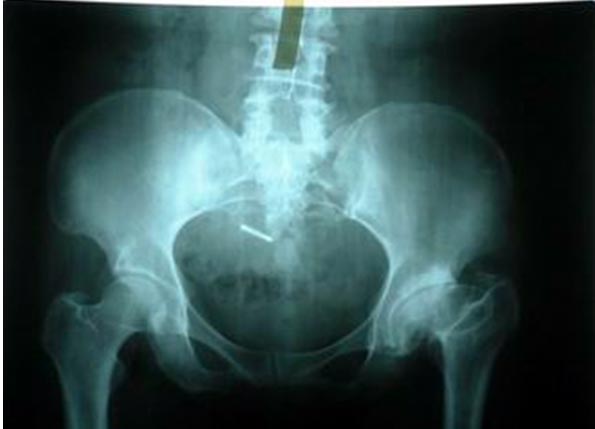

患者为髋臼嗜酸性肉芽肿,髋臼有骨破坏,患者有疼痛症状。刮除病灶后,采用生物固定全髋关节置换术。

术后4年复查,病灶没有复发,假体没有松动,关节功能良好。